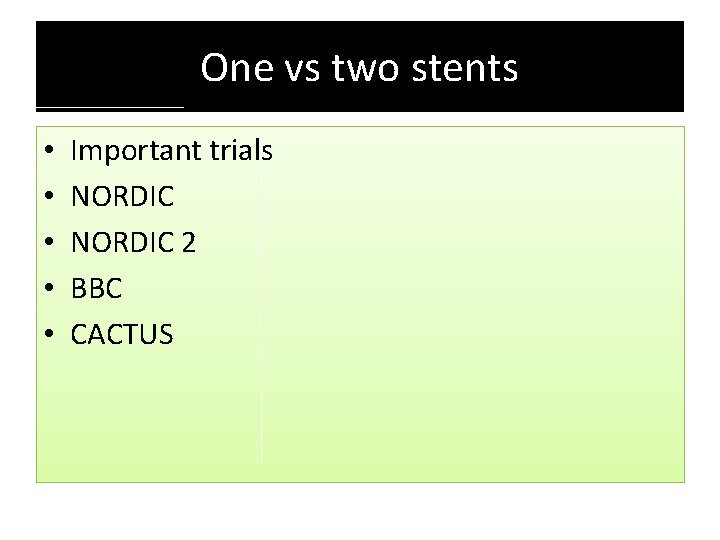

One vs two stents • • • Important trials NORDIC 2 BBC CACTUS